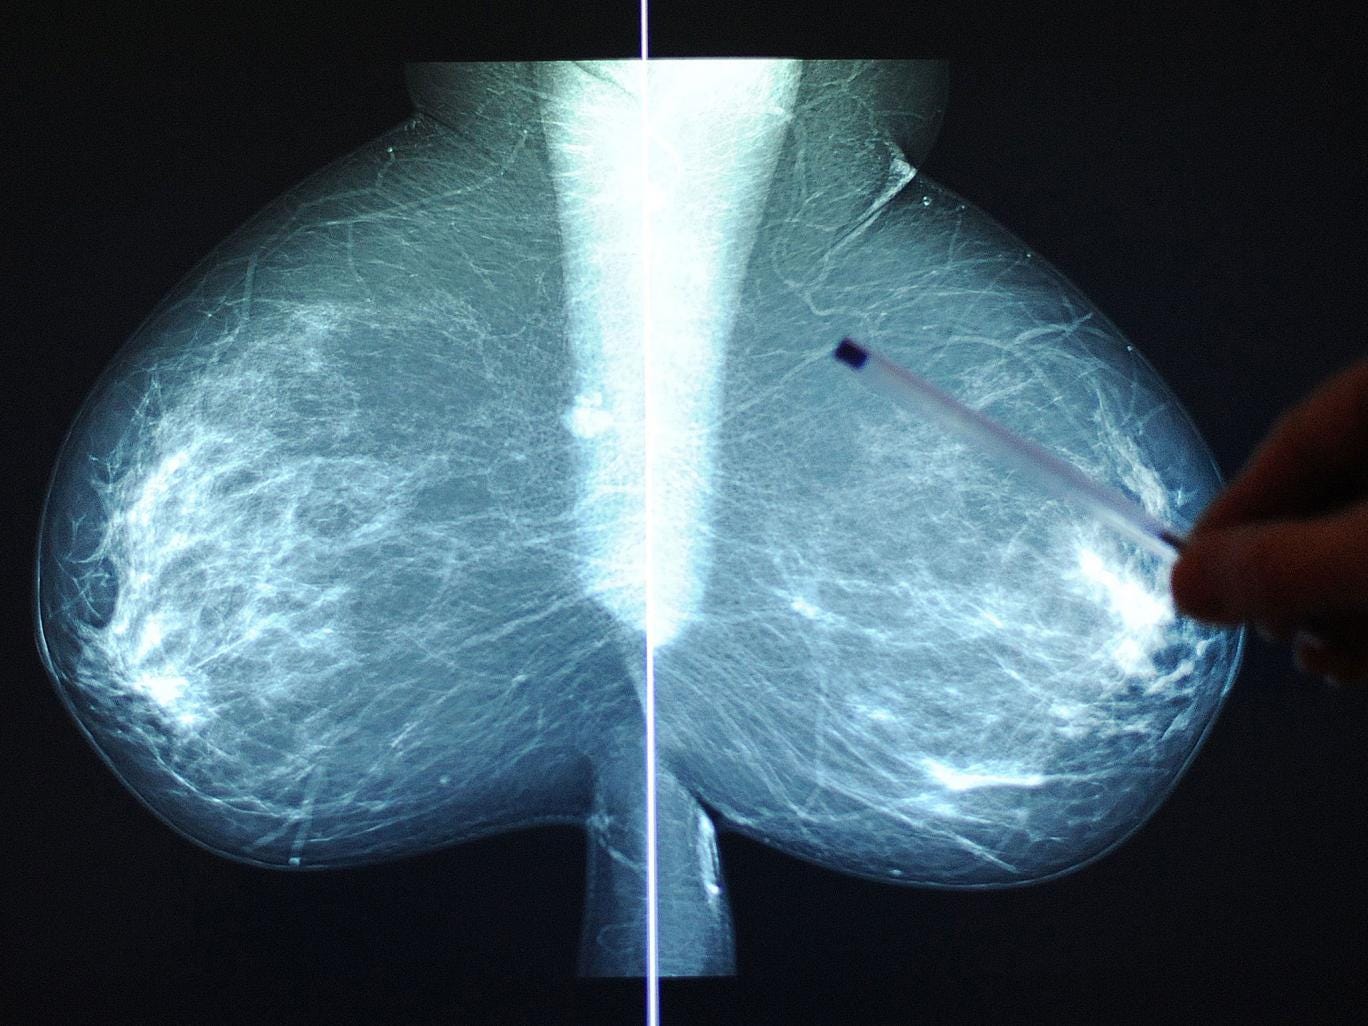

The risk is even greater for some individual cancers, with the risk of breast cancer in women increasing by 20 per cent for every 10cm increase in height, while malignant melanoma increases by about 30 per cent for every 10cm height increase for both men and women, the study found.